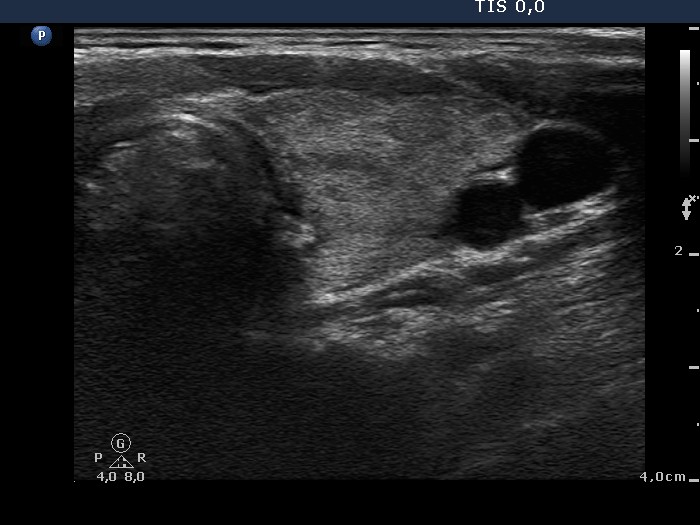

Follow-up investigation 33 months after first visit (ultrasonographic picture 4)

Patient on daily 20 mg methimazole therapy in euthyroid state

Left lobe, transverse view. Great part of this lobe is echonormal.